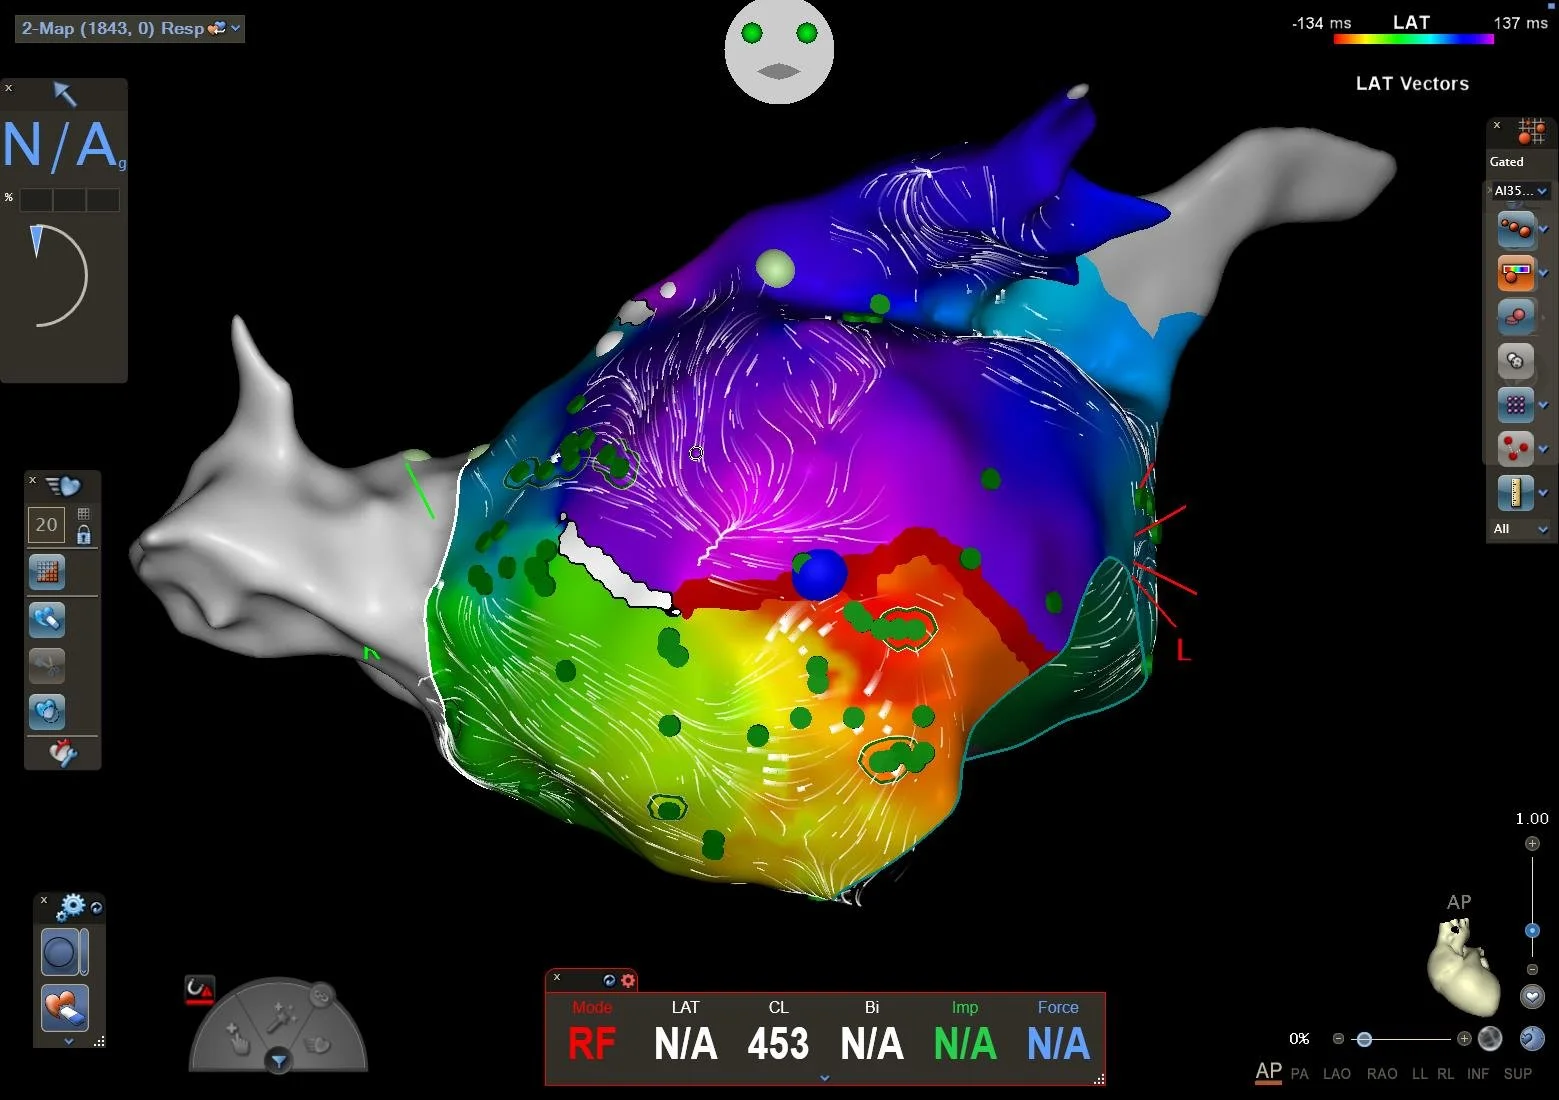

3D Navigation einer Vorhofflimmerablation, ultrahochauflösend

Im Rahmen spezieller elektrischer Herzkatheteruntersuchungen können wir die Reizleitungseigenschaften des Herzens untersuchen - hierzu werden über die Leiste elektrische Herzkatheter am Herzen positioniert und über Provokationsmanöver die Herzströme vermessen. Auftretende Rhythmusstörungen können unter Verwendung eines hochmodernen 3D-Navigationssystems mit Röntgen-Bildfusion genau kartiert werden, und können prinzipiell auch Strahlen- und Kontrastmittelfrei erfolgen. In gleicher Sitzung kann dann auch die Verödung der Herzrhythmusstörung erfolgen.

Im Rhythmuszentrum Oberlausitz der Oberlausitz Kliniken führen wir die Verödung aller Vorhofrhythmusstörungen durch, inklusive Vorhofflimmern, AV-Knoten Reentry Tachykardien,, Tachykardien bei angeborenen zusätzlichen Herznerven (WPW Syndrom), ektope atriale Tachykardien („zusätzliche Zündkerze in den Vorhöfen“), typischen und atypischen Vorhofflattern. Dank modernster Katheter- und Mapping-Technologien können wir auch hoch-komplexe Folgeeingriffe nach Voreingriffen mit hoher Erfolgsaussicht und niedrigster Komplikationsrate durchführen.